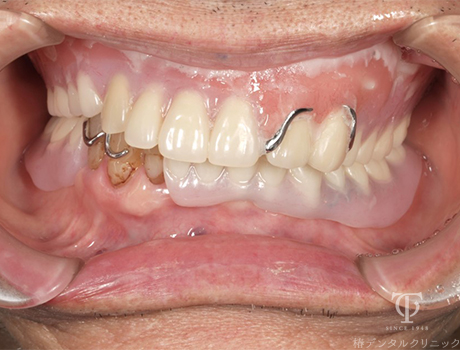

Case02

- 症状

- 右上の痛み

- 治療期間

- 約2年

- 治療費用

- (上顎)メタルボンド:132,000円×7本

(上顎)部分床義歯:550,000円

(下顎)インプラント治療:473,000円×3本

(下顎)オールセラミッククラウン:110,000円×4本

右上の歯肉の痛みで来院されました。歯周病やかみ合わせに問題があり患者様と相談の上、インプラントと部分床義歯にてかみ合わせを再構築しました。

【リスク・副作用】

インプラント治療後、痛みや違和感、出血、腫れなどが出る事があります。喫煙者、糖尿病などの方の場合、歯が生着しない場合があります。入れ歯を清潔に保たないと虫歯や歯肉炎、歯周病になるリスクがあります。